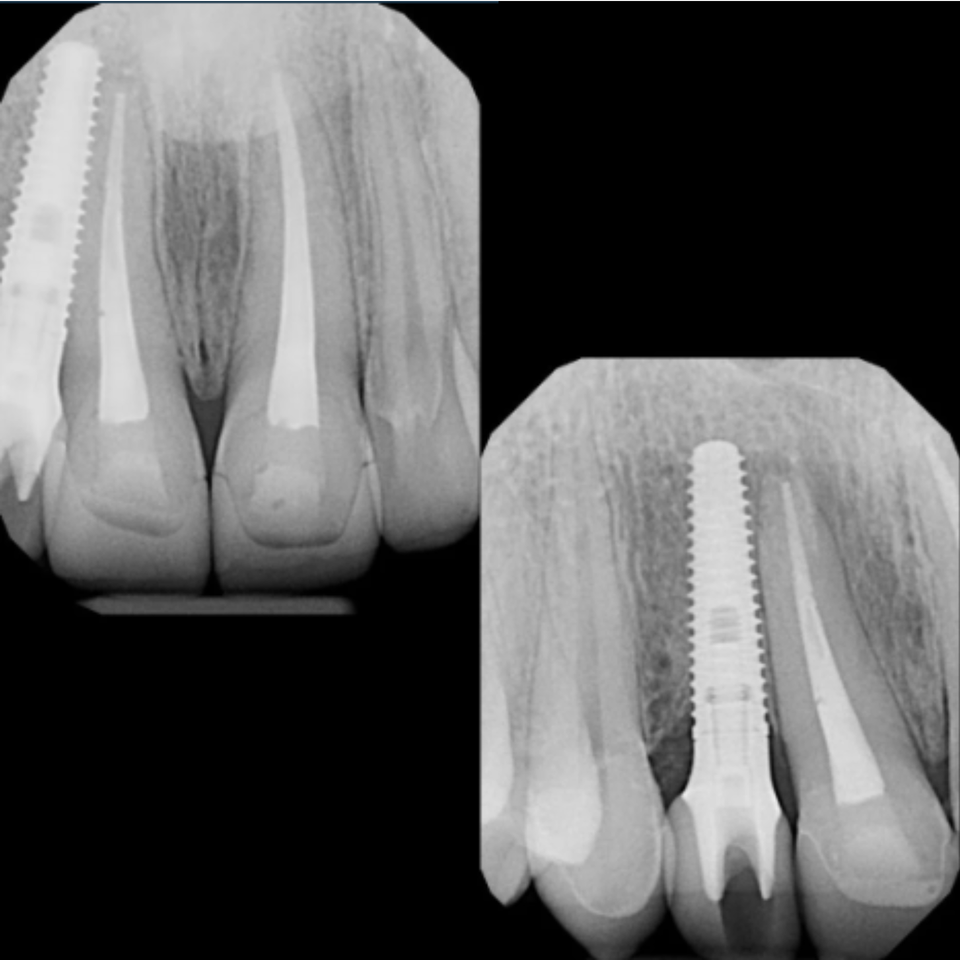

In another case, we provided emergency treatment involving root canal therapy for the upper central incisors. After careful evaluation, we placed an immediate implant for the right lateral incisor and performed a crown lengthening procedure to ensure proper restorative support.

To maintain both function and esthetics during healing, we placed a provisional bridge. After a four-month healing period, we finalized the treatment by placing custom crowns on the central incisors and restoring the implant with its permanent crown.

The result was a stable, natural-looking restoration that preserved both structure and smile aesthetics.